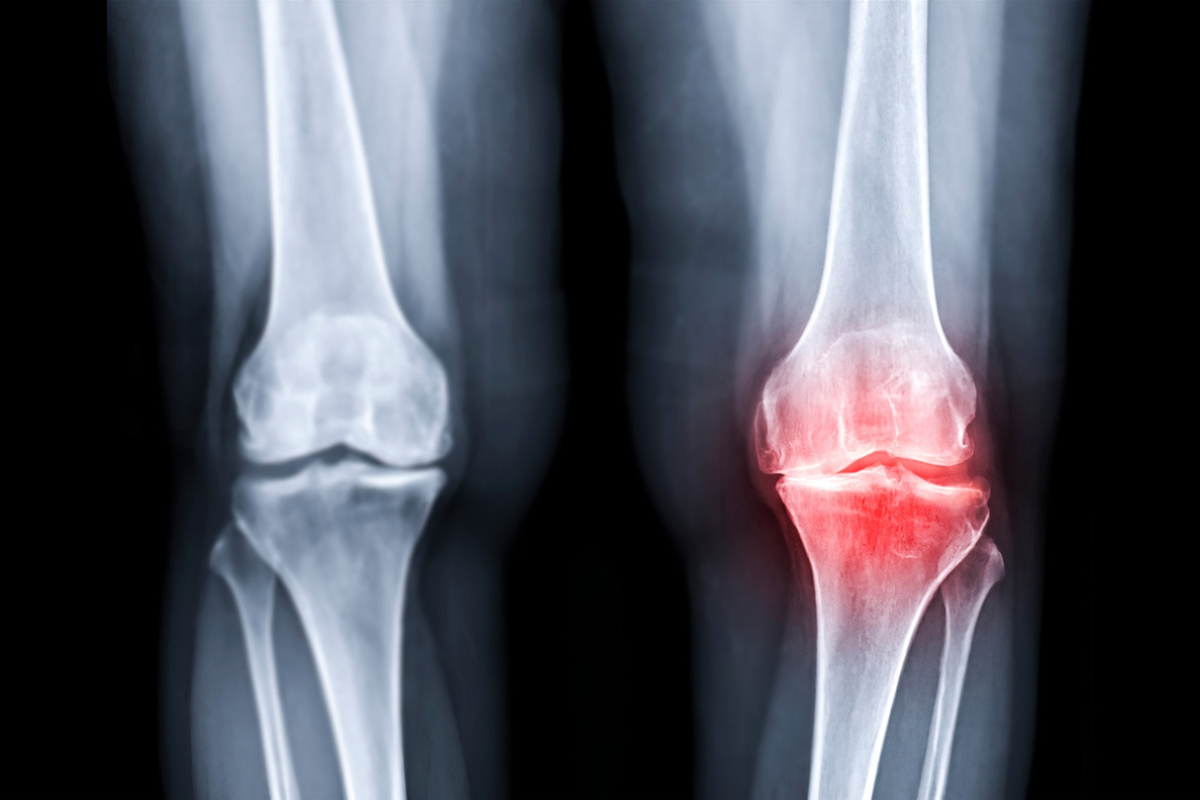

退化性關節炎,也叫骨關節炎,是一種因關節長期使用、軟骨逐漸磨損所造成的不適症狀。最常發生的地方像是膝蓋、髖關節、手指,會讓人感覺關節卡卡、喀喀響,甚至走樓梯、蹲下都會痛。

關節中的「軟骨」就像是骨頭與骨頭之間的保護墊,幫助我們在走路、跑跳、蹲坐時減少摩擦與撞擊。但這層保護墊並不會像皮膚一樣自然再生,隨著時間或使用頻率增加,它會逐漸變薄、破損,甚至消失。

當軟骨磨損後,骨頭之間會直接接觸,就容易引發不適,例如喀喀聲、痠痛、僵硬等問題。這也是為什麼退化性關節炎會讓人覺得「膝蓋在磨」、「站久會痛」。